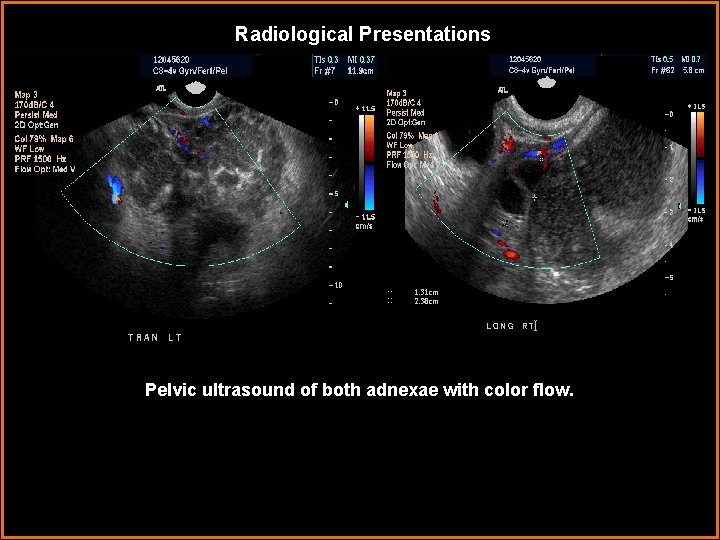

Radiological Presentations Pelvic ultrasound of both adnexae with color flow.

Findings and Differentials Findings: The pelvic ultrasound demonstrates complex, thick walled, multi-cystic masses in the adnexae, bilaterally. The cysts contain internal debris. The ultrasound of the right upper quadrant demonstrates diffuse hypoechoic, sub-centimeter masses in all lobes of the liver. The CT confirms the findings on US. No adenopathy is present in the CT images. Differentials: • Ovarian CA with liver metastases. • Bilateral tubo-ovarian abscesses with liver micro-abscesses. • Bilateral tubo-ovarian abscesses and unrelated liver metastases from breast CA. • Multiple liver abscesses from pyogenic infection and unrelated ovarian CA.